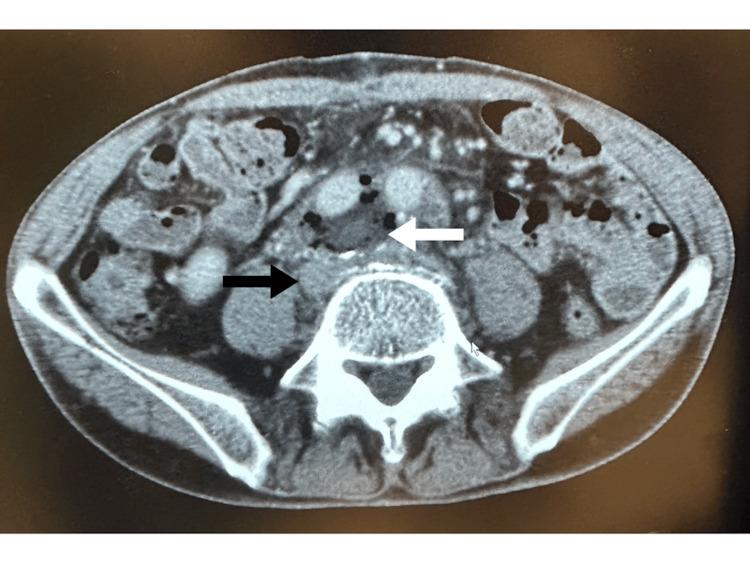

Addressing venous bleeding is a frequent complication of vascular and abdominopelvic surgeries. We present a novel sutureless repair technique using Hydrofit (Terumo, Tokyo, Japan), an elastomeric sealant. In a patient experiencing common iliac vein bleeding during abdominal aortic aneurysm surgery, this technique successfully achieved complete hemostasis. By applying the elastomeric sealant with an autologous arterial patch to the bleeding site, we demonstrate the simplicity and effectiveness of sutureless hemostasis for venous bleeding.

处理静脉出血是血管和腹部盆腔手术中常见的并发症。我们介绍一种使用弹性密封剂Hydrofit(日本东京泰尔茂公司生产)的新型无缝合修复技术。在一名腹主动脉瘤手术中出现髂总静脉出血的患者身上,该技术成功实现了完全止血。通过将弹性密封剂与自体动脉补片应用于出血部位,我们证明了无缝合止血治疗静脉出血的简便性和有效性。